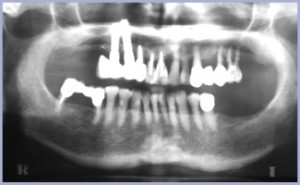

Paziente di sesso femminile di anni 74, affetta da parodontopatia cronica a lenta evoluzione che presenta marcata atrofia delle selle (figg. 1-3). La protesi al 2° quadrante data da oltre 20 anni e non risulta più adeguata alla funzione masticatoria per estrema mobilità sotto carico (fig. 4).

- Fig. 1